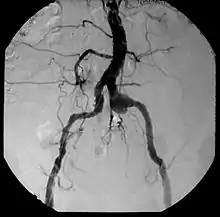

| Aneurysm, a commonly lethal complication of SA | |